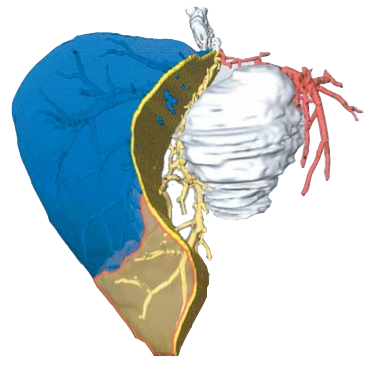

MEDICAL TREATMENT

Virtual Resection